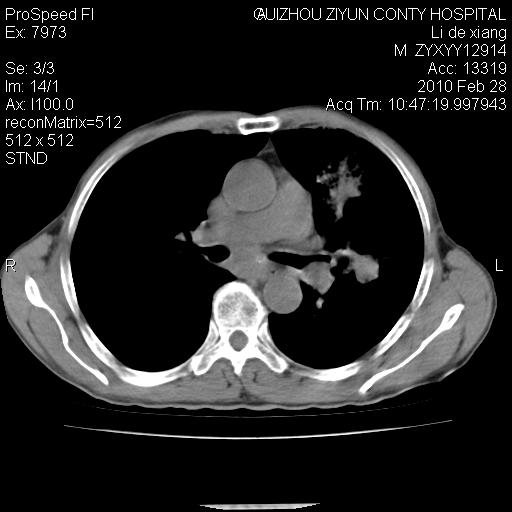

标题: CT24776:男 71Y 咳嗽咳痰胸痛两月,伴声音嘶哑。 [打印本页]

标题: CT24776:男 71Y 咳嗽咳痰胸痛两月,伴声音嘶哑。

左侧中央型肺癌伴左肺上叶阻塞性肺炎及节段性不张可能性大,建议纤支镜检查!

左侧中央型肺癌伴左肺上叶阻塞性肺炎及节段性不张可能性大,建议纤支镜检查!纵隔淋巴结转移.

左侧中央型肺癌伴左肺上叶阻塞性肺炎及纵隔淋巴结转移。

左肺门部肿块,伴左上肺斑块影,周边模糊,支持左肺中央型肺癌伴节段性不张及阻塞性肺炎,结合支气管镜检查。

左上叶支气管狭窄,阻塞性病变,肺门肿块,纵隔及肺门淋巴结增大,中央性肺癌

左肺中央型肺癌并阻塞性改变、纵膈 淋巴结转移

左侧中央型肺癌伴左肺上叶阻塞性肺炎及纵隔淋巴结转移

支持 左肺中央型肺癌伴左肺上叶阻塞性肺炎,纵隔淋巴结转移。